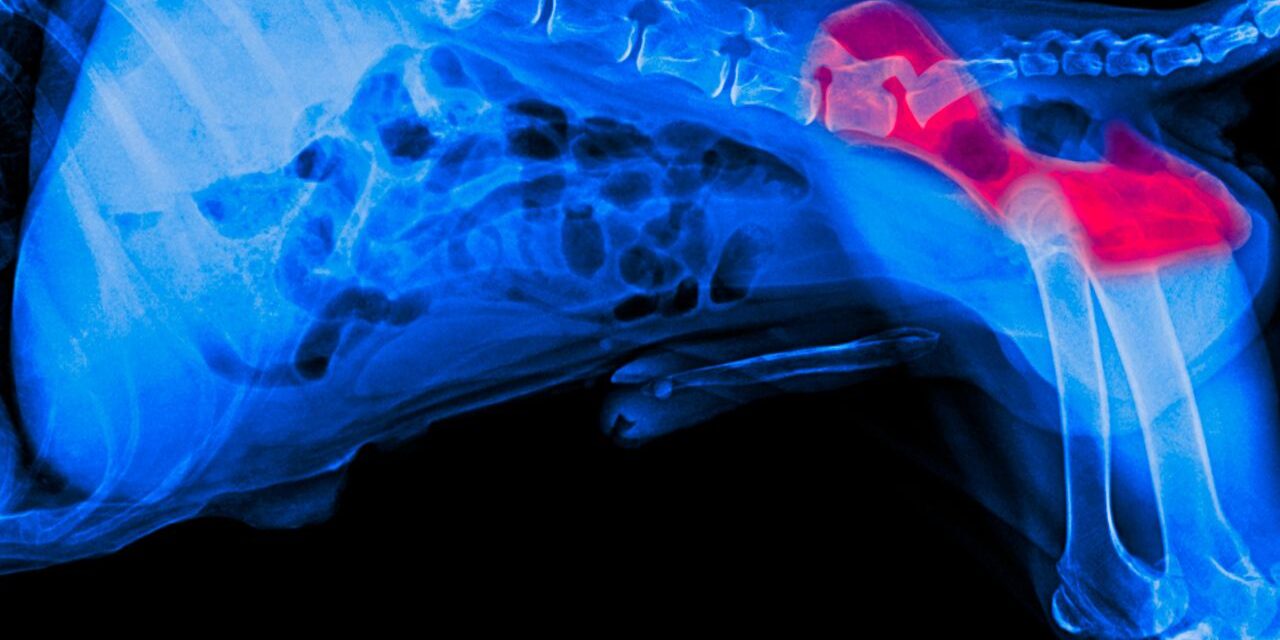

Dysplazja stawów to poważne schorzenie układu ruchu, które prowadzi do deformacji i niewłaściwego funkcjonowania stawu biodrowego lub łokciowego. W zdrowym stawie główka kości udowej pasuje idealnie do panewki miednicy, tworząc płynny ruch. W przypadku dysplazji te elementy nie współpracują prawidłowo, co powoduje ból, stan zapalny i stopniowe zwyrodnienie stawu.

Dysplazja stawu biodrowego u psa czy dysplazja łokciowa u psa występuje częściej u psów dużych i szybko rosnących. Szczególnie narażone są labrador retriever, owczarek niemiecki, golden retriever, bernardyn, rottweiler czy nowofundland.